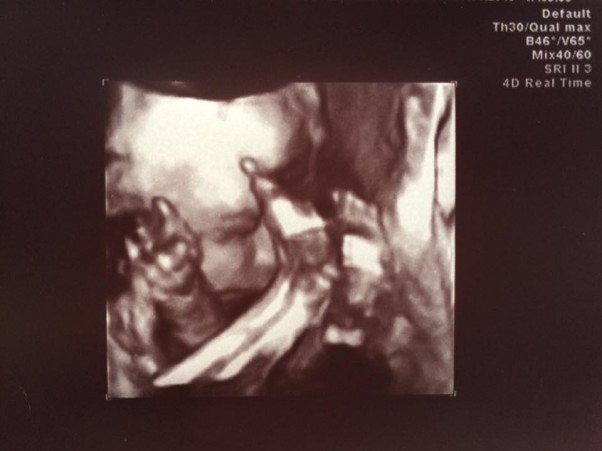

Z Elizą wszystko dobrze, ma około 700g, leży narazie miednicowo, zasłonięta rączkami i stópkami, tylko tyle nam pokazała:)